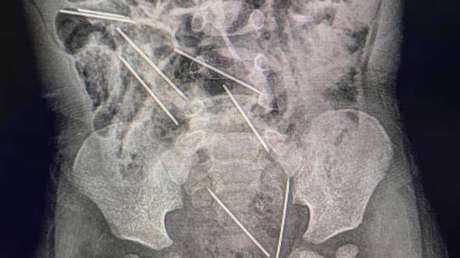

Las agujas se alojaron en distintas partes del cuerpo del menor: dos estaban en el peritoneo en el lado derecho, tres en el izquierdo, una en la pared abdominal y otras dos se encontraban “peligrosamente” entre la vejiga y el recto, reportan medios locales.